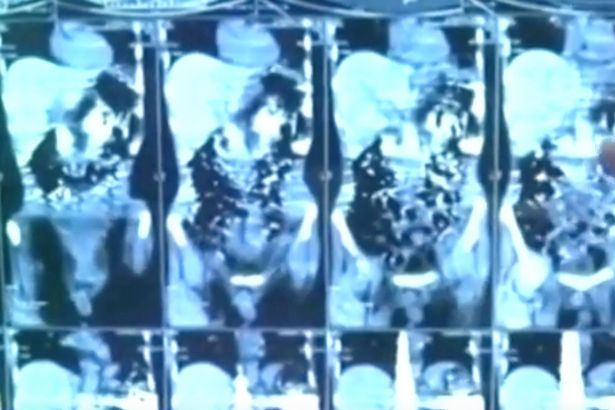

Các ảnh chụp X-quang dạ dày của bệnh nhân khiến các bác sĩ kinh ngạc khi nhìn thấy hơn 40 mảnh kim loại.